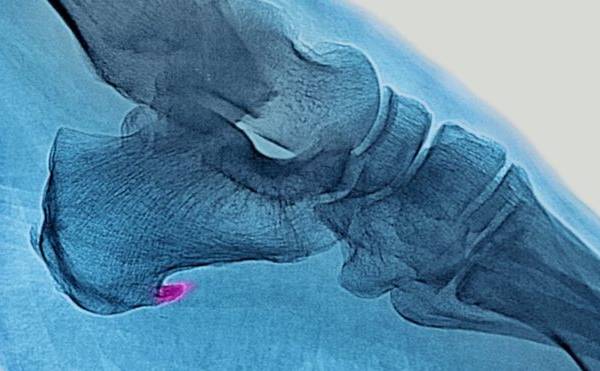

Se trata de un dolor agudo en la planta del pie, justo por delante del talón, que se intensifica cuando nos levantamos o pasamos un período de tiempo sin movernos.

Lo que ocurre es que se produce una inflamación de la membrana que recubre la musculatura de la planta del pie y el talón.

La inflamación se produce cuando se trata compensar con los músculos del pie y sus tendones un desbalance que ocurre en el cuerpo.

Eso se debe a que la fascia plantar cumple una función biomecánica al caminar de absorber y devolver la energía que se produce cuando el pie impacta contra el suelo.